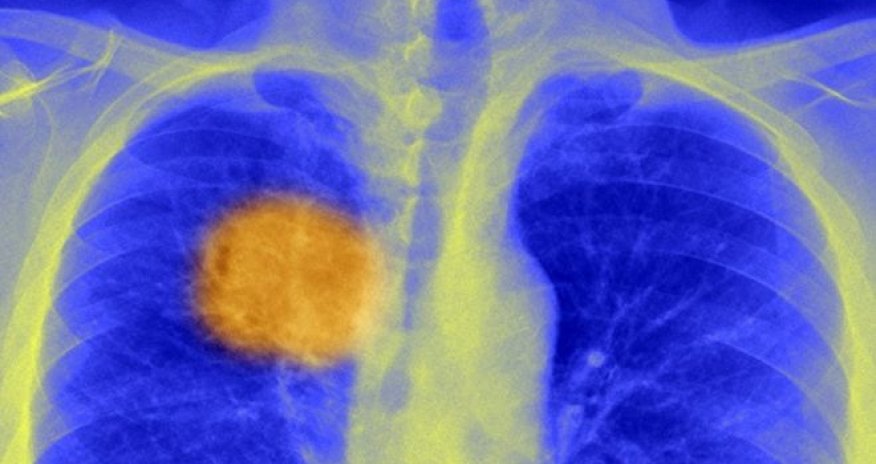

Scientists 'find cancer's Achilles heel'

Scientists believe they have discovered a way to "steer" the immune system to kill cancers.

They have developed a method, reported in Science journal, for finding unique markings within a tumour - its "Achilles heel" - that the immune system can target.

The problem is cancers are not made up of identical cells - they are a heavily mutated, genetic mess and samples at different sites within a tumour can look and behave very differently.

They grow a bit like a tree with core "trunk" mutations, but then mutations that branch off in all directions. It is known as cancer heterogeneity.

The international study developed a way of discovering the "trunk" mutations that change antigens - the proteins that stick out from the surface of cancer cells.